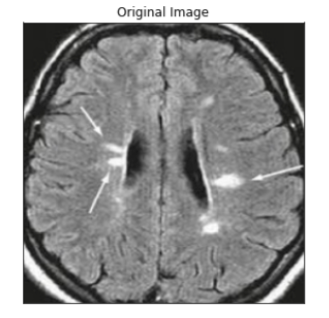

Diagnosing a brain tumor begins with Magnetic Resonance Imaging (MRI). Once MRI shows that there is a tumor in the brain, the most regular way to infer the type of brain tumor is to glance at the results from a sample of tissue after a biopsy/surgery.

An MRI uses magnetic fields, to produce accurate images of the body organs. It can be used to measure the tumor’s size. A special dye called a contrast medium is given before the scan to create an accurate snd clearer picture. This dye can be injected into a patient’s vein or given as a pill or liquid.

MRIs create more accurate snd clearer pictures than CT scans and are the favored way to diagnose a brain tumor. The MRI may be of the brain, spinal cord, or both, depending on the type of tumor presumed and the plausibility that it will spread in the CNS. There are different types of MRIs and the results of a neuro-test, done by the neurologist, help determine which type of MRI to use.